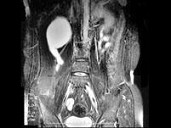

多项选择题女,31岁, 右侧腰部胀痛不适,MRI检查如图所示, 下列说法正确的是 ( )

A、右肾重度积水

B、右侧输尿管粗细不均并迂曲扩张

C、右侧输尿管下段呈囊样扩张

D、左肾输尿管未见异常

E、考虑为右侧输尿管囊肿